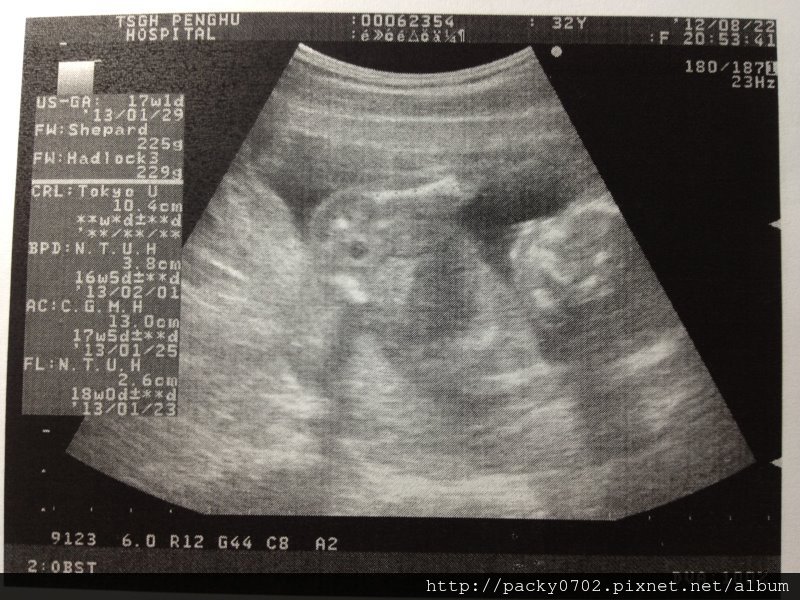

超音波檢查,醫生說道寶寶的手臂腿骨都很長、脊椎也是完整的,

而小寶寶在照超音波時,還俏皮的翹起小拇指,感覺有點娘呀~

上頭那長長的就是他的大腿骨啦,聽說遺傳了媽媽的長腿喔~

20120822 (5)

寶寶:身長10.4cm,頭圍3.8cm,肚圍13.0cm,大腿骨長2.6cm,重量225g